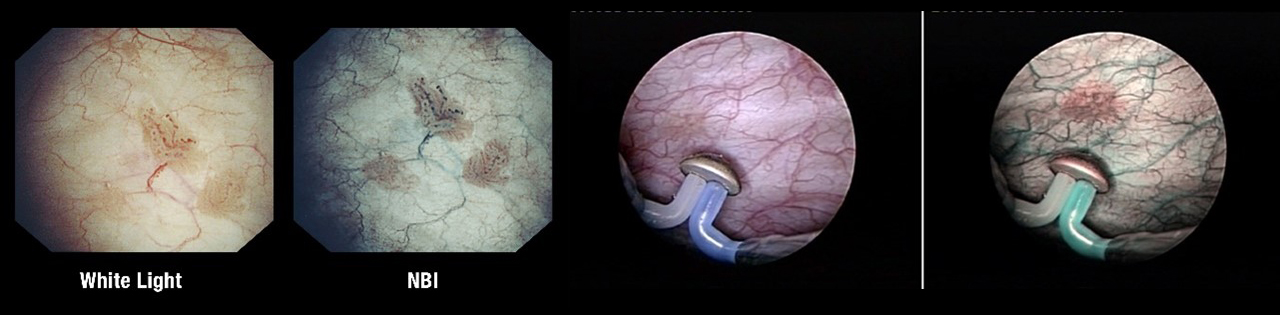

Цистоскопия является ключевым методом диагностики рака мочевого пузыря – эндоскопический осмотр мочевого пузыря через мочеиспускательный канал. Существует принципиально два вида эндоскопов для проведения цистоскопии: ригидный цистоскоп (жесткий металлический инструмент, более подходящий для женщин, и гибкий инструмент, повторяющий сложную анатомию мужской уретры. Сегодня в клинике Хадасса в арсенале отделения урологии используются самые современные эндоскопы.

Разновидности цистосокпов:

Вид опухоли при цистоскопии:

Стандартная цистоскопия обычно выполняются при так называемом «белом» освещении. Однако, некоторые образования могут оставаться невидимыми при таком освещении, что привело к разработке новых методов визуализации опухоли.

Один из таких методов — это узкополосная визуализация (NBI). Исследования показали, что использование NBI при осмотре мочевого пузыря значительно увеличивает частоту выявления рака.